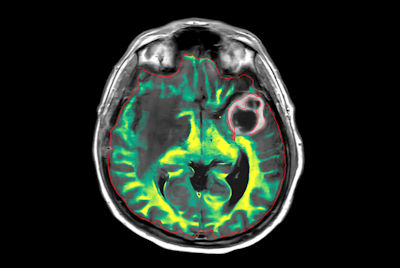

Large lesion brain imaging with synthetic MRI